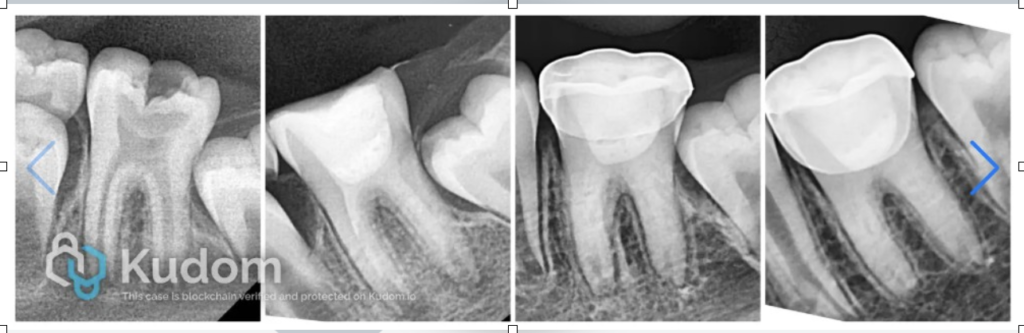

An 8-year-old female patient reported to the clinic with complaint of pain in left mandibular molar tooth. Clinical and radiographic examinations revealed a carious nonvital 36 with immature root apex. The stage of root maturity corresponded with Demirjian’s stage G (wide open apical foramen and nearly completed root length).

The X-ray shows deep carious lesion in tooth 36. The root length is nearly complete with wide open apical foramina and indistinct apical lamina dura around both mesial and distal roots.